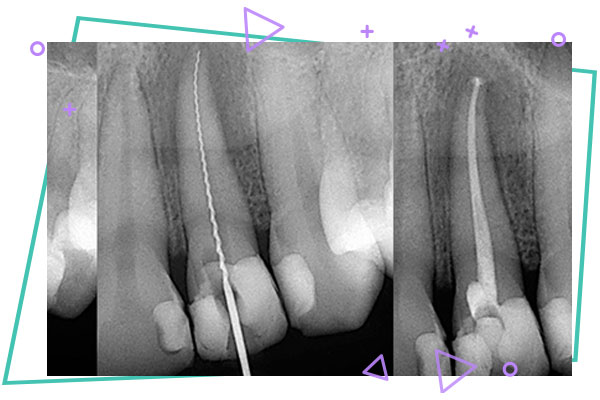

ابتدا پوسیدگی ها و عوامل عفونی در قسمت تاج دندان برداشته می شود . سپس کانال های ریشه دندان تعین طول شده و محتویات آن ها به وسیله ابزارهای سوهان مانند پاکسازی می شوند و در نهایت کانال های دندان بعد از شست و شو و ضد عفونی با مواد شبیه پلاستیک که از صمغ یک نوع گیاه تهیه شده اند و کاملا با بدن انسان سازگارند ، پرشده و مهر و موم می گردند .

از روش های جدید دیگر استفاده از دستگاه تعیین طول الکترونیکیک ریشه ها با ایکس لوکیتور می باشد که دقت درمان را افزایش داده و دفعات عکس گرفتن را کاهش می دهد . از دیگر تغییرات مهم این حوزه استفاده از رادیوگرافی های دیجیتال است که میزان دریافت اشعه ایکس به مقدار چشمگیری کاهش می یابد .